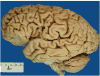

Context: Autopsy evaluation of the brain of a patient with frontotemporal dementia (FTD) can be daunting to the general pathologist. At some point in their training, most pathologists learn about Pick disease, and can recognize Pick bodies, the morphologic hallmark of Pick disease. Pick disease is a type of frontotemporal lobar degeneration (FTLD), the general category of pathologic process underlying most cases of FTD. The 2 major categories of pathologic FTLD are tauopathies (FTLD-tau) and ubiquitinopathies (FTLD-U). Pick disease is one of the FTLD-tau subtypes and is termed FTLD-tau (PiD).